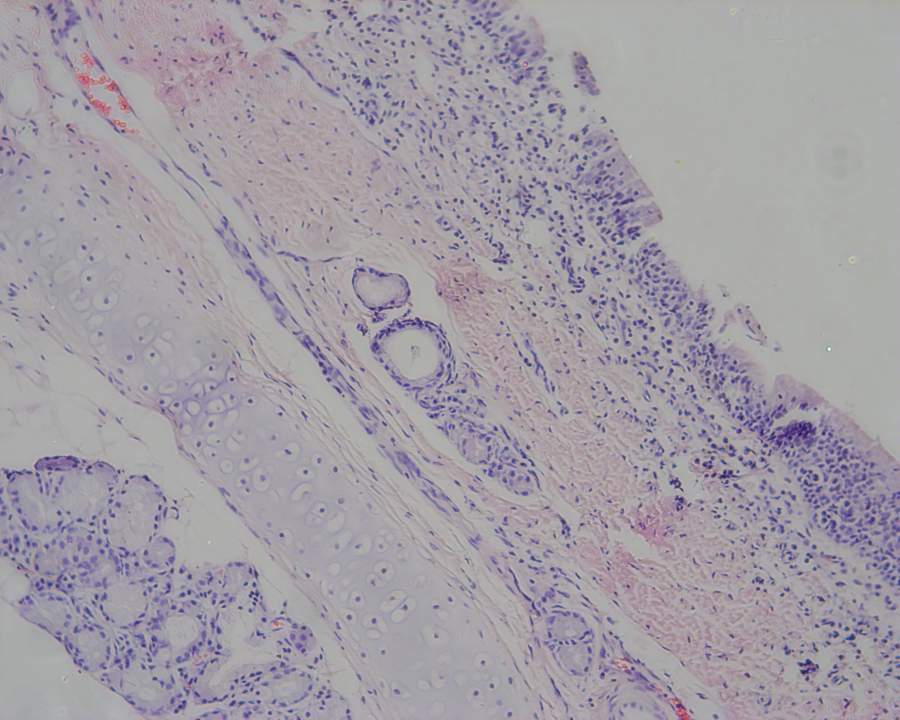

HE染色后怎么描述组织无损伤?